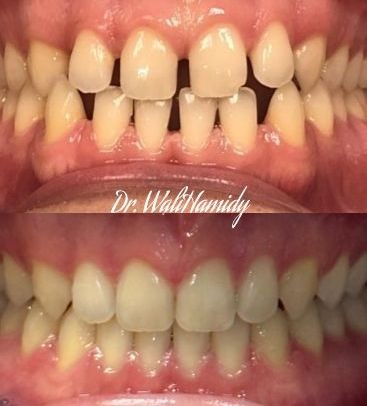

Check out our Invisalign® treatment gallery to see how this orthodontic service can straighten your teeth and improve your smile. Contact La Jolla Dental Image at 858-202-0481 today to make an appointment with our dentist, Dr. Wali Hamidy, and learn more about Invisalign clear aligners in La Jolla, California.